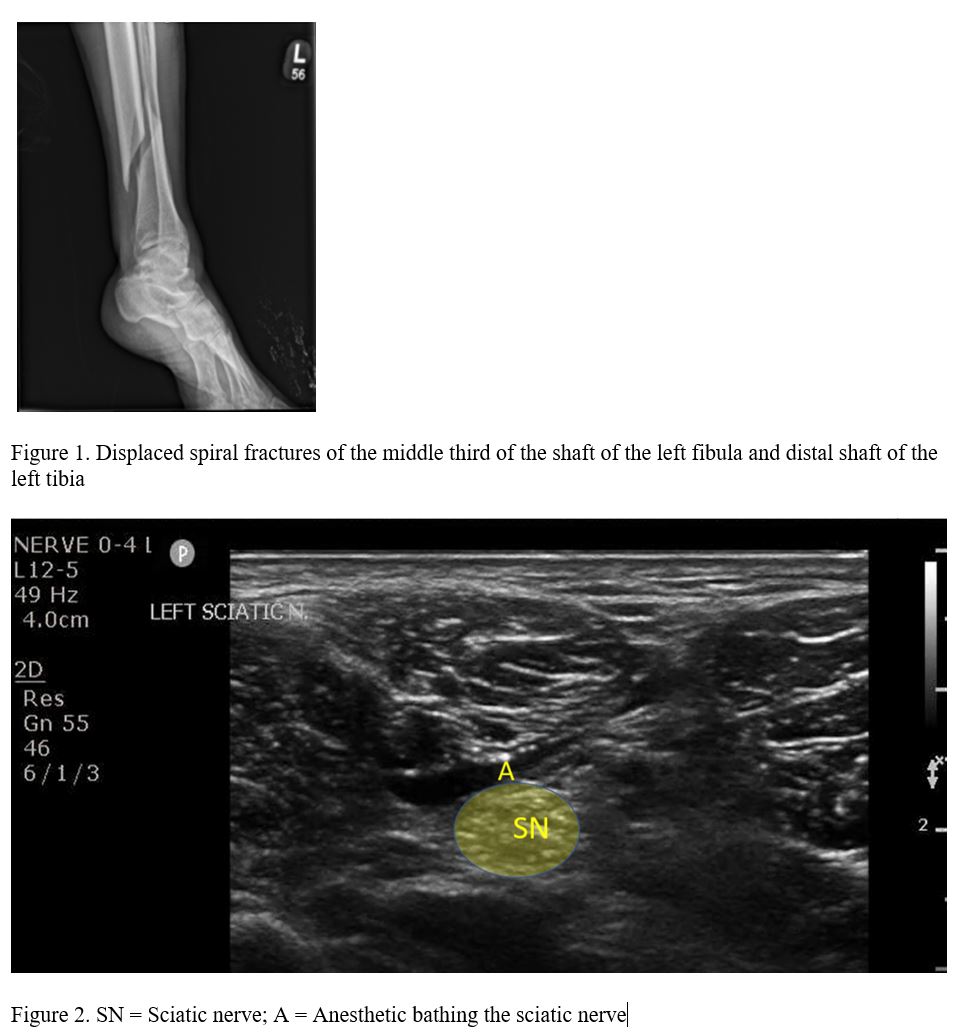

The patient was found to have displaced spiral fractures of the middle third of the shaft of the left fibula and distal shaft of the left tibia (Figure 1). On arrival, the patient received 50mcg of IV fentanyl, and one hour later he received 5mg of IV morphine.